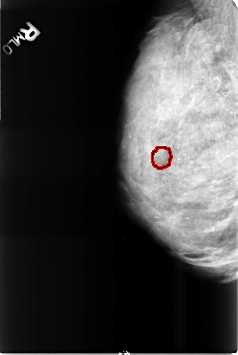

B_3469_1.RIGHT_MLO

RIGHT_MLO LINES 4608 PIXELS_PER_LINE 3088 BITS_PER_PIXEL 12 RESOLUTION 50 OVERLAY

FILE: B_3469_1.RIGHT_MLO.OVERLAY

TOTAL_ABNORMALITIES 1

ABNORMALITY 1

LESION_TYPE CALCIFICATION TYPE PUNCTATE-PLEOMORPHIC DISTRIBUTION CLUSTERED

ASSESSMENT 4

SUBTLETY 2

PATHOLOGY BENIGN

TOTAL_OUTLINES 1

BOUNDARY